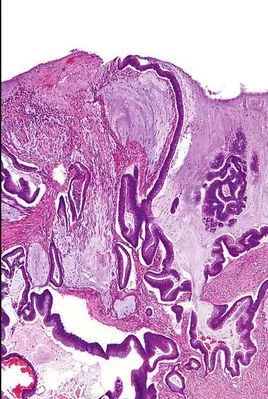

粘儿了控试结部老脸液腺癌 , 当癌细胞分泌粘液较明显时,称为粘液腺癌。乳头状型1例,癌细胞核异型性明显,核仁大,核分裂像易见。实体型2来自例,分化低异型性高。

当癌细胞分泌粘液较明显时,称为粘液腺来自癌.乳头状型1例,癌细胞核异型性明显,核仁大,核分裂像易见.实体型2例,分化低异型性高